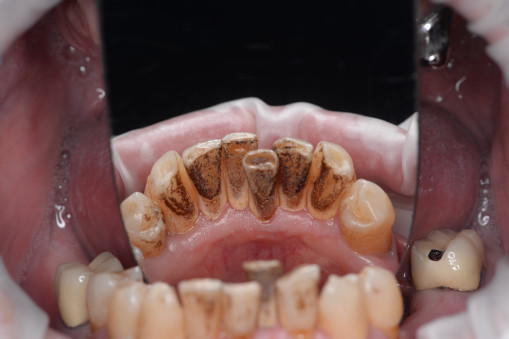

А прежде, чем вы посмотрите фотографии «до» и «после» лечения слизистой оболочки полости рта, проведенных в нашей клинике, хочу поблагодарить большое количество наших пациентов, которые поверили, прониклись нашей концепцией, и мы вместе, именно вместе победили болезни десны, гингивит и пародонтит!

До/после лечения